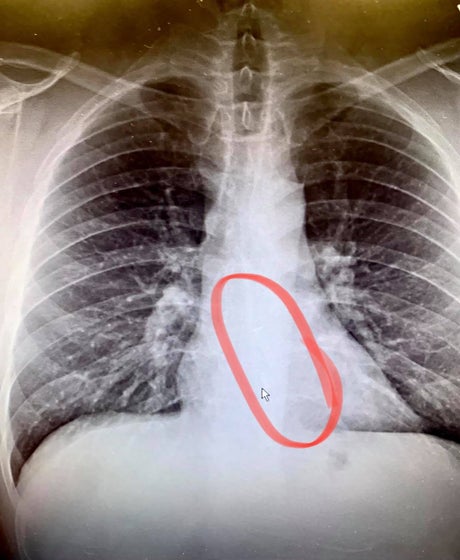

But following x-rays, shocked doctors discovered that the culprit was indeed one of the pods, around two inches long, and wedged firmly inside his throat for nearly 24-hours.

'They were all jaws aslack, looking at this x-ray, on the screen where you could see it in such clear definition,' Gauthier said.

Posting photos of the x-ray on Facebook, the father called it “one for the record books” and warned AirPod users: “Be careful listening to wireless headphones when you fall asleep, you never know where they'll end up!”